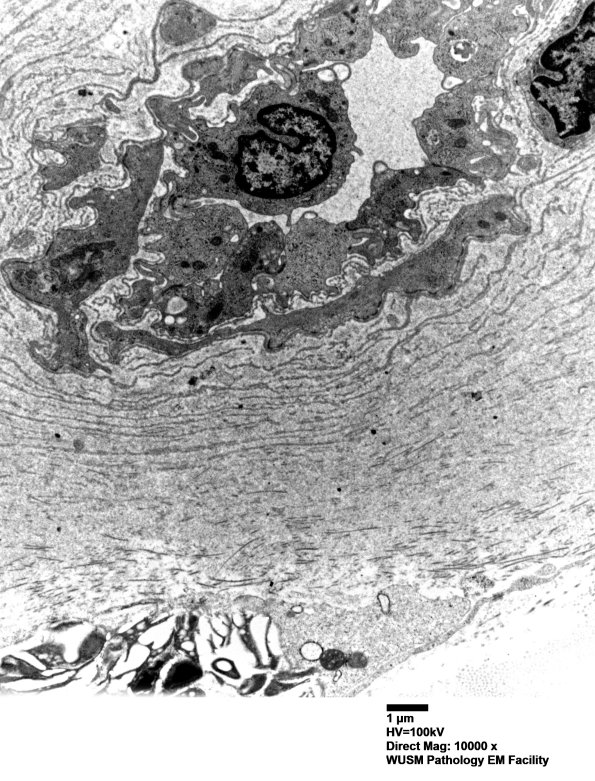

Washington University Experience | VASCULAR | Hypoxia-Ischemia, fetal-neonatal | White Matter | 6C2 (Case 6) EM 003 - Copy

6C2 (Case 6) EM 003 - Copy